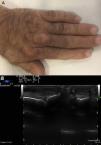

Presentación del caso clínicoVarón de 59 años exfumador, hipertenso y con hipercolesterolemia de larga evolución tratada con estatinas, aunque con escasa adherencia. Cardiopatía isquémica que comienza como IAMSEST Killip II hace un año, con enfermedad coronaria de 3 vasos que precisó de revascularización quirúrgica con cuádruple bypass. Varios familiares de primer grado presentaron cardiopatía isquémica prematura e hipercolesterolemia. En la exploración física no presentaba arco corneal ni xantelasmas, y sí engrosamiento de los tendones Aquiles y presencia de xantomas tendinosos en los nudillos de ambas manos (fig. 1A, fig. 2A). No tenía soplos cardiacos ni carotídeos. Obesidad troncular (talla 1,78m, peso 97,5kg, IMC 30,8kg/m2, perímetro de cintura 108cm), PA: 120/65mmHg, no visceromegalias. Pulsos distales palpables y simétricos.

Se solicita una ecografía para evaluar los xantomas, que objetivó engrosamiento de los tendones Aquiles (D>I)2 con pérdida de su estructura fibrilar homogénea, con un área en su interior en el tercio medio hipoecoica, compatible con xantomas a este nivel3,4. Así mismo se observa la misma imagen ecográfica en varios tendones extensores de las manos (fig. 1B, fig. 2B).